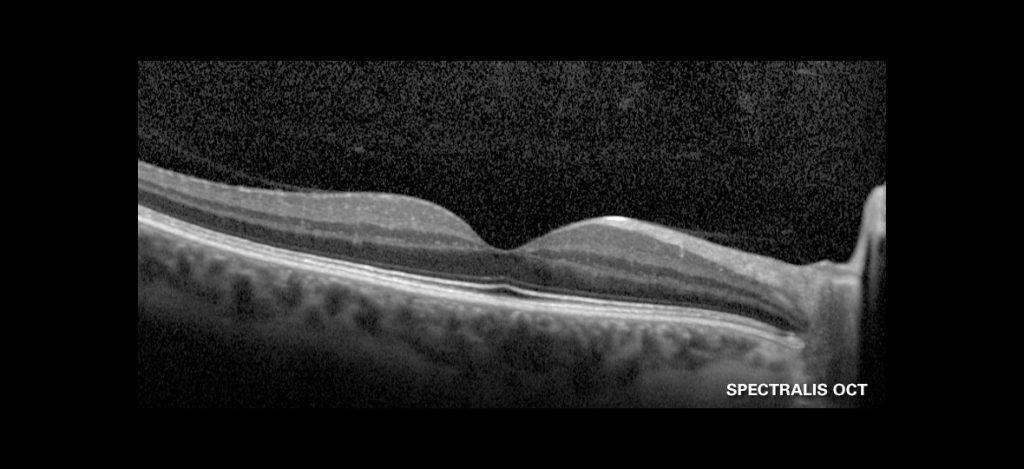

Visualização de 10 Camadas

O SPECTRALIS® oferece imagens OCT de alta resolução para visualização de 10 camadas da retina, ajudando você a descrever e identificar com confiança as patologias.